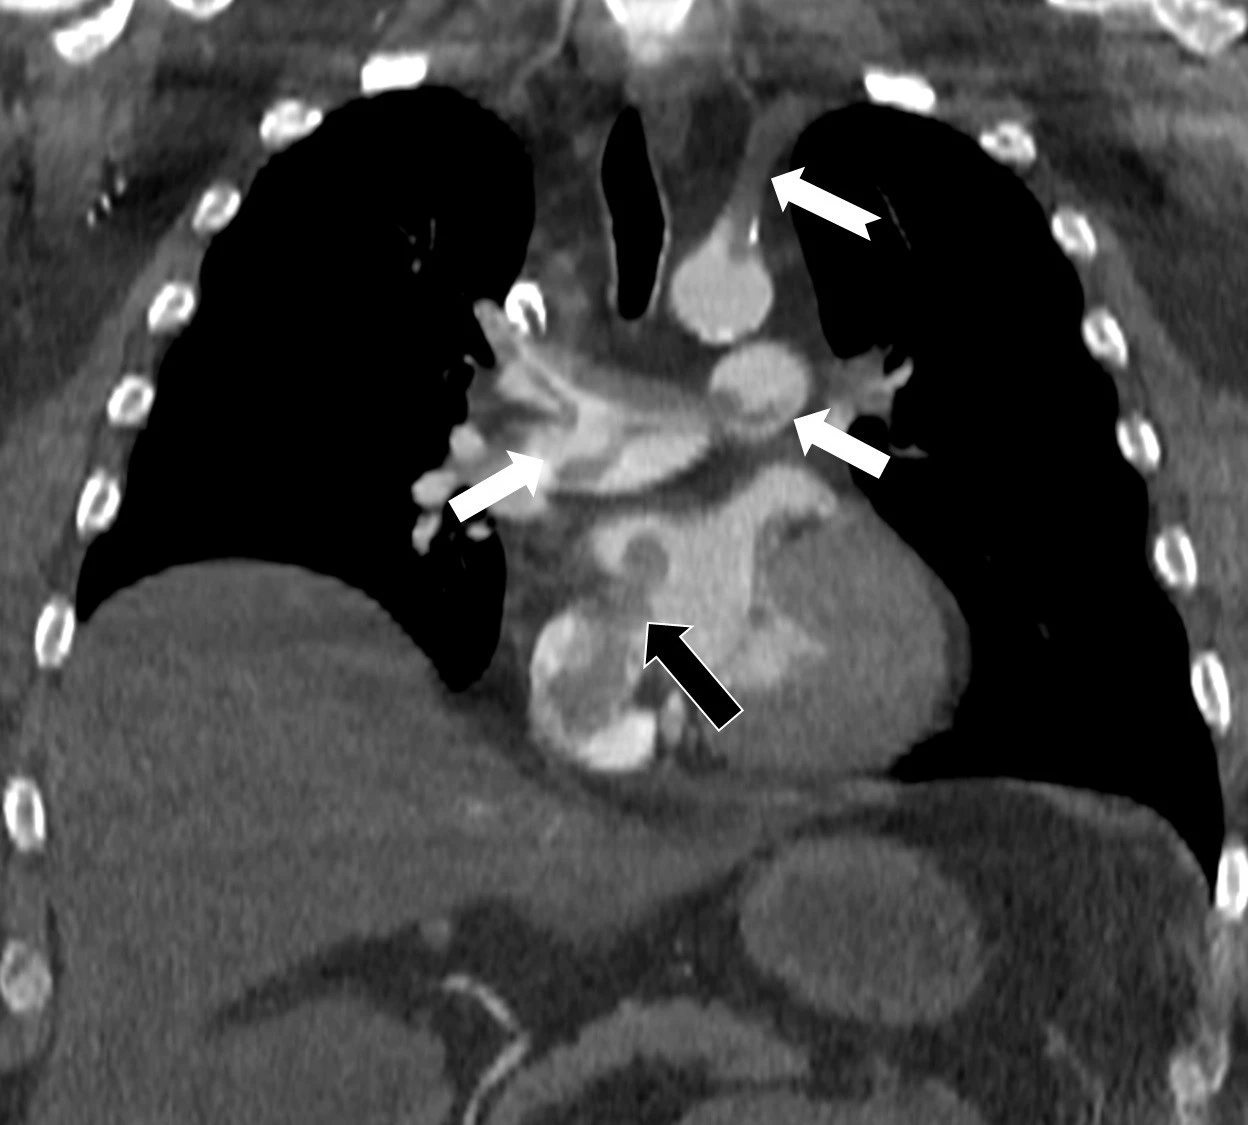

Özel Denizli Tekden Hastanesi’nde görev yaptığı dönemde de başarılı çalışmalara imza atan Radyoloji Uzmanı Prof. Dr. Nevzat Karabulut, kalpteki gizli deliklerin hayatı tehdit eden paradoks emboliye neden olabildiğini ortaya koydu. Kalp ve akciğer görüntülemesi alanındaki uluslararası bilimsel çalışmalarıyla tanınan Radyoloji Uzmanı Prof. Dr. Nevzat Karabulut, dünyanın önde gelen tıp dergilerinden Radiology dergisinin 2025 Kasım sayısında yayımlanan "Paradoxical Embolism with Clot-in-Transit in Atrial Septal Defect" adlı çalışmasında, penis ameliyatından 5 gün sonra ani göğüs ağrısı, nefes darlığı ve kol uyuşması şikâyetiyle hastaneye başvuran 60 yaşındaki bir hastada, daha önce fark edilmemiş kalp odacıkları arasındaki bir delikten geçen pıhtının hayati tehlike oluşturduğunu ortaya koydu. Bir dönem Özel Denizli Tekden Hastanesi’nde de görev yapan Prof. Dr. Nevzat Karabulut’un yaptığı çalışmada; akciğerin bilgisayarlı tomografi anjiyografisi sayesinde toplar damarlardan kaynaklanan pıhtının akciğer damarlarını tıkaması yanında, kalpteki delik nedeniyle kalbin sağ tarafından sol tarafına geçerek ana atardamara ulaştığı ve sol kol damarını tıkadığı gösterildi. Emboli görüntülemesi konusunda çok sayıda bilimsel çalışması bulunan Prof. Dr. Karabulut, genelde bacak damarlarından kaynaklanan pıhtıların ölümcül olabilen akciğer embolisine yol açması yanında, kalp deliği olan hastalarda ana atardamar yoluyla beyin, kol ve bacak gibi vücudun diğer bölgelerine de geçerek ani damar tıkanmasına (paradoks emboli) bağlı bulgulara yol açtığını belirtti. Prof. Dr. Karabulut’un çalışmasında nedeni bilinmeyen pıhtı atmalarında kalpteki gizli deliklerin mutlaka araştırılması gerektiği vurgulanarak ekokardiyografi ve bilgisayarlı tomografi tetkiklerinin erken ve doğru tanı koymada hayat kurtarıcı rolüne dikkat çekildi.